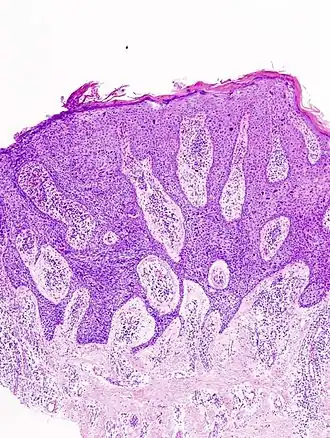

Image de la maladie de Bowen au microscope.

La maladie de Bowen est un carcinome épidermoïde (ou spinocellulaire) intra-épidermique (carcinome in situ), favorisé par le soleil et l'arsenic. Elle peut toucher la peau mais aussi les muqueuses[1]. Elle se présente sous la forme d'une lésion brun rougeâtre arrondie ou arciforme bien limitée dont la surface est un peu surélevée et squameuse[1]. Son diagnostic est histologique. Son évolution est très lente et la maladie présente un excellent pronostic de guérison. En revanche, en l'absence d'un diagnostic et d'un traitement approprié, elle évolue lentement mais sûrement vers un véritable carcinome épidermoïde invasif[1].